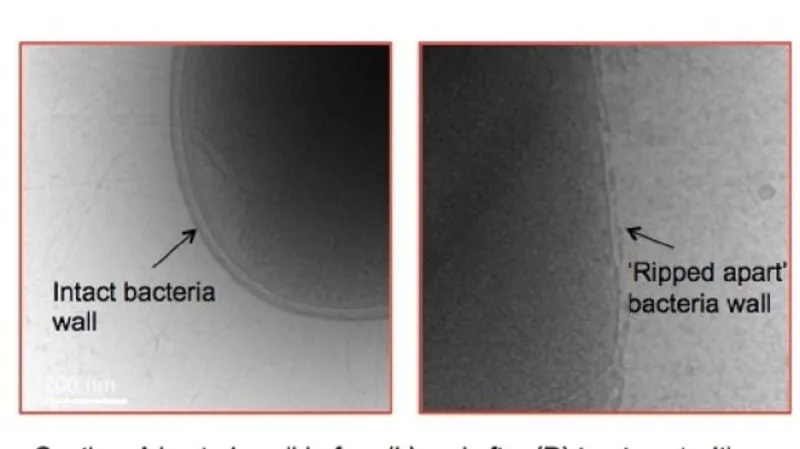

„Objevili jsme, že tyto polymery opravdu cílí na bakterie a ničí je rovnou několika způsoby,“ řekla Lam v rozhovoru pro deník Telegraph. „Jedním z nich je fyzicky narušit nebo rozbít buněčně stěny bakterie. To v ní vyvolá takový stres, že se začne sama ničit.“

Lék dostal jméno SNAPP. Jde o nanotechnologií vyrobené polymerní peptidy – chemické sloučeniny organického původu. Každý polymer má 16-32 paží, takže připomíná hvězdičku. Pomocí nich útočí na bakterie: Tyto makromolekuly propojené peptidovou vazbou napadají mikroby zcela přímo, fyzickou likvidací buněčných stěn bakterií.